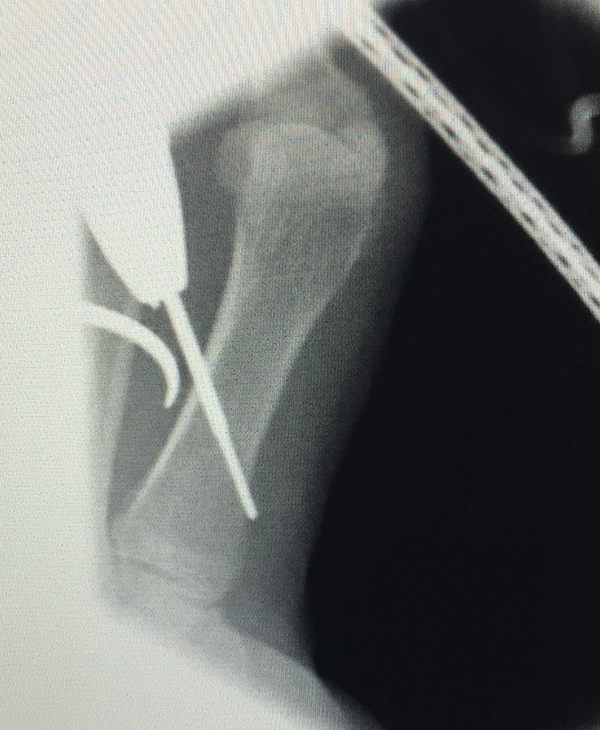

Werden komplette Osteotomien an den Zehen durchgeführt, fädeln wir die Osteotomien mit einem 1.2 oder 1.4 mm Kirschner-Draht auf, damit die einzelnen Fragmente nicht verkippen (Abb. 22).

Abb. 22 a-d: Präoperative Klauenzehen beim Jugendlichen in zwei Ansichten (a-b) und postoperative Auffädelung mit Kirschner-Drähten linker und rechter Fuß (c-d).

Nach unserer Erfahrung können komplette Osteotomien nicht so gut in einem Tapeverband stabil gehalten werden. Im Fall von Derotationen kombinieren wir einen Draht mit externen Tapezügeln, um das Ergebnis zu sichern. Die Drähte werden 2-3 Wochen belassen und anschließend in der Sprechstunde gezogen. Anschließend wird die Zehe noch 2 weitere Wochen mit Tape gezügelt (Abb. 23).